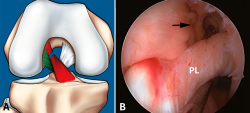

Figura 7. Rotura parcial del fascículo anteromedial (AM). A: esquema que ilustra una rotura parcial del ligamento cruzado anterior (LCA) afectando al fascículo AM; B: imagen artroscópica de la rodilla izquierda desde el portal anterolateral. Rotura completa del fascículo AM (flecha) con un fascículo posterolateral (PL) intacto y tenso a la exploración con el palpador.

Sin embargo, a pesar de estos esfuerzos, la valoración de la actitud terapéutica no se basa en los hallazgos de RM. Si bien la valoración combinada de la exploración clínica y los hallazgos de RM permite establecer una sospecha de inestabilidad en una lesión parcial del LCA, la exploración bajo anestesia con la maniobra de pivot shift sigue siendo el test más fiable en la valoración funcional del LCA y el tratamiento quirúrgico definitivo se debe basar en la exploración artroscópica(17)(Figuras 7 y 8).

Figura 8. Rotura parcial del fascículo posterolateral (PL). A: esquema que ilustra una rotura parcial del ligamento cruzado anterior (LCA) afectando al fascículo PL; B: visión artroscópica de la rodilla derecha desde el portal anterolateral. Se observa una rotura completa del fascículo PL (flecha), tras la separación con el palpador del fascículo anteromedial (AM).